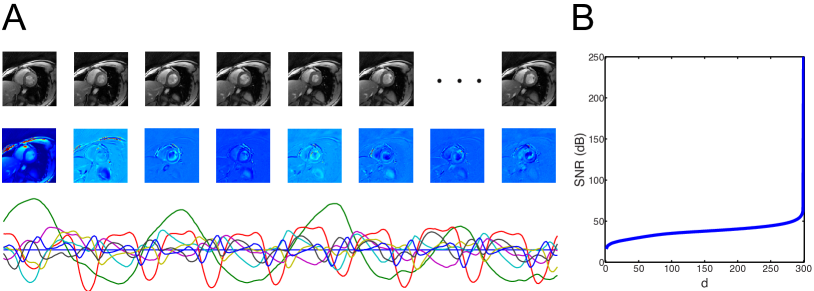

We first illustrate the concept of LDS model using a sample video, see Figure 1(A). With such a model, observations 𝐲tsubscript𝐲𝑡\mathbf{y}_{t} can be represented as linear transformation of the state 𝐱tsubscript𝐱𝑡\mathbf{x}_{t}, corrupted by observation noise, whereas the states 𝐱tsubscript𝐱𝑡\mathbf{x}_{t} evolve according to a first-order Markov process corrupted by process noise. The noise terms ωtsubscript𝜔𝑡\mathbf{\omega}_{t} and νtsubscript𝜈𝑡\mathbf{\nu}_{t} are assumed to be temporally white, independent of each other, the states and the observations. If the noises are assumed to be zero-mean Gaussian spatially, then the LDS model corresponds to a first-order Gaussian Markov random process. We focus on the Gaussian noise case throughout this paper, with ωt𝒩(0,Q)similar-tosubscript𝜔𝑡𝒩0𝑄\mathbf{\omega}_{t}\sim\mathcal{N}(0,Q) and νt𝒩(0,R)similar-tosubscript𝜈𝑡𝒩0𝑅\mathbf{\nu}_{t}\sim\mathcal{N}(0,R).

Refer to caption

Figure 1: (A) Illustration of the LDS model for a sample heart video: (top) sequence of individual frames of a video Y𝑌Y, (middle) observation matrix C𝐶C, (bottom) state sequence X𝑋X. (B) LDS as a good approximation of the original video, where we plot SNR as a function of d𝑑d.

In the case where dnmuch-less-than𝑑𝑛d\ll n, the motion manifold is a good model to reduce the high-dimensional video cube into a low-dimensional representation. We illustrate such a concept in Figure 1(B). The key promise of using LDS relies on the assumption that high-dimensional signal 𝐲tnsubscript𝐲𝑡superscript𝑛\mathbf{y}_{t}\in\mathbb{R}^{n} can be faithfully represented using low-dimensional state sequence 𝐱tdsubscript𝐱𝑡superscript𝑑\mathbf{x}_{t}\in\mathbb{R}^{d}, with dnmuch-less-than𝑑𝑛d\ll n.

which is a function of d𝑑d. We obtain reasonably good SNR even at low d𝑑d, as shown in Figure 1(B).